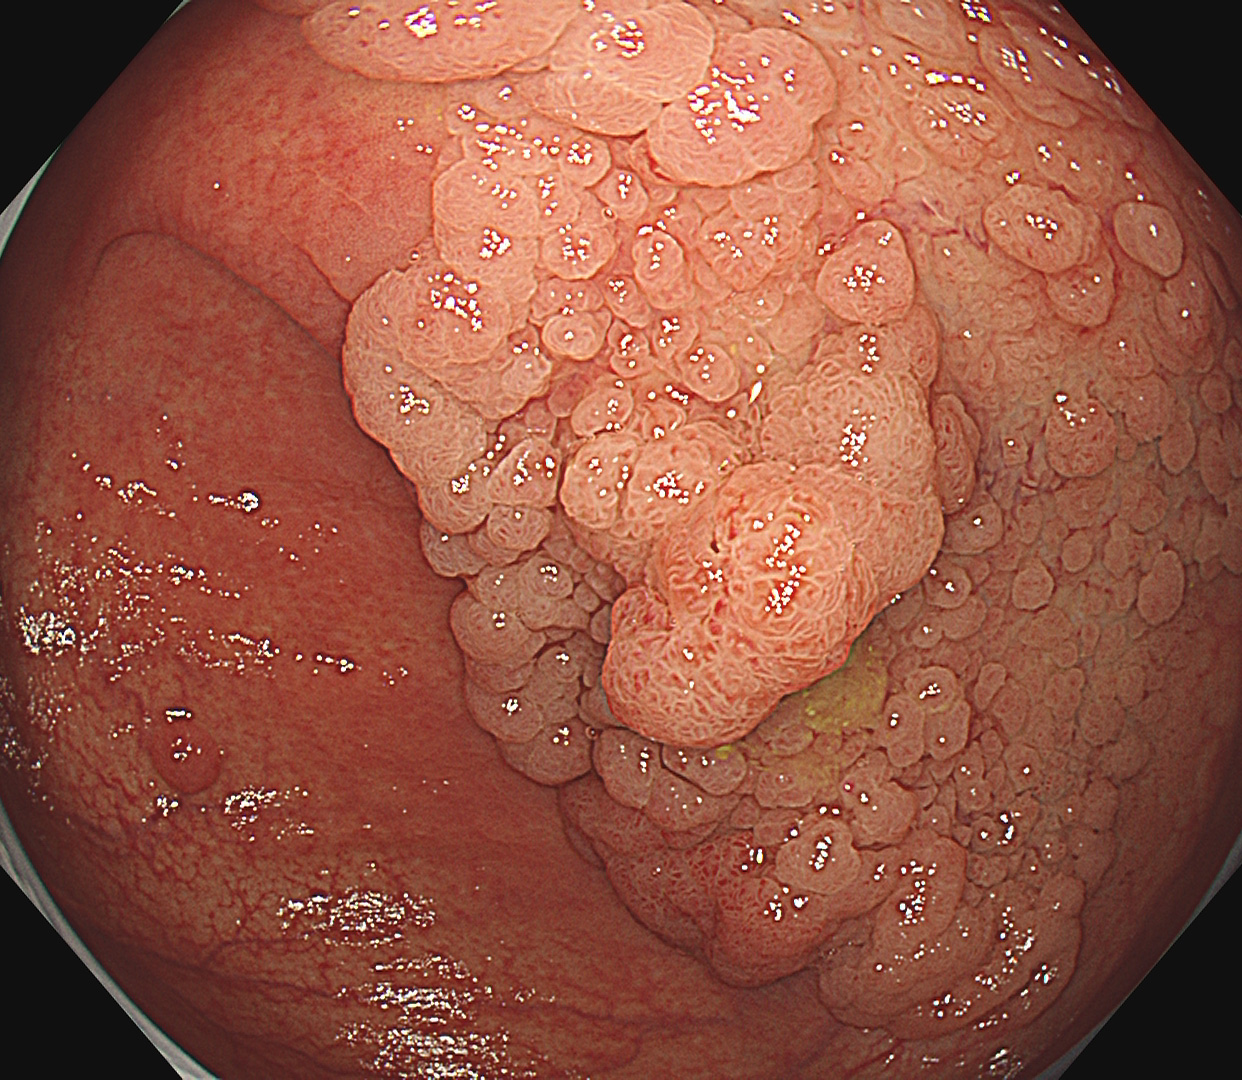

早期大腸癌(LST-G)ESD

- EMR・ESD による早期消化管癌の低侵襲治療

- 咽頭・十二指腸・大腸を含む高難度 ESD に対応